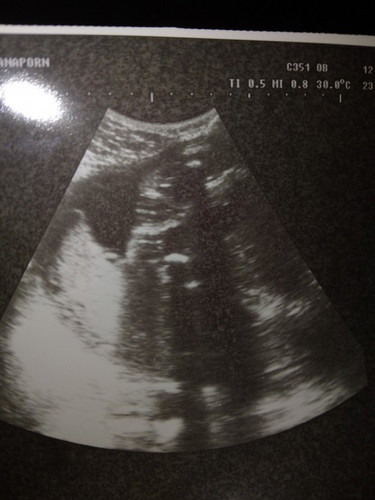

รูปอัลตร้าซาว

แม่ๆพอจะมองออกไหมค่ะ ญ หรือ ช ยังไม่ทราบเพศน้องไม่กล้าถามคุณหมอค่ะ #ท้องแรกคะ #ขอบคุณล่วงหน้านะคะ

ดูเองแทบดูไม่ออกจริงๆคะคงมีแต่คุณหมอที่ดูออก😅

ดูไม่ออกเลยค่ะ